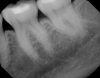

Fig 10. Decay evident, teeth J and K, on x-ray of caries-prone 6-year-old patient.

Figure 10

Fig 11. Transillumination image confirmed caries.

Figure 11

In another case of a caries-prone 6-year-old patient, the clinician, who generally avoids taking x-rays on children, opted to take them this time because lesions can grow rapidly.13 The transillumination caries detector also was used to attain a more complete diagnosis and to find problems as early as possible. Decay appeared on both the x-ray (Figure 10) and the CariVu image (Figure 11). Viewing the situation from multiple perspectives enables treatment to be as conservative as possible because the clinician can pinpoint exactly where the decay is present on the tooth.